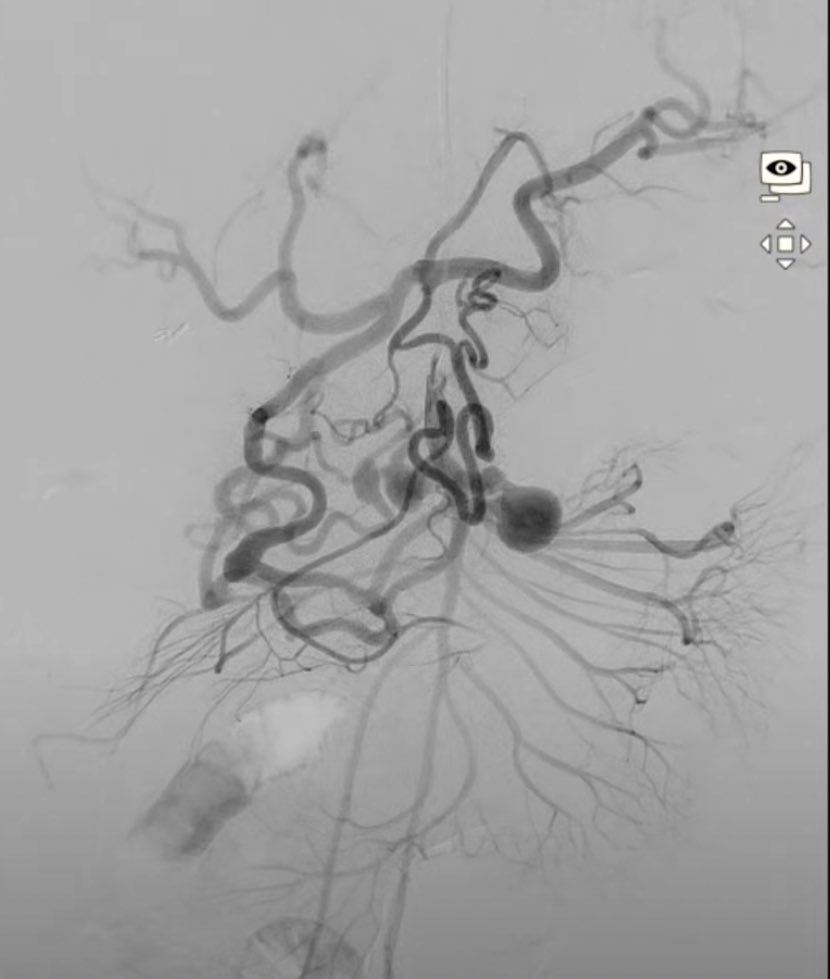

We authored an article for Medical Professionals CLT highlighting Genicular Artery Embolization (#GAE)—an innovative treatment for #kneepain caused by osteoarthritis. #irad @theobserver @wcnc @SIRspecialists